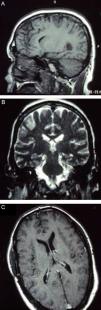

La paquimeningitis hipertrófica crónica (PHC) es un proceso inflamatorio de etiología desconocida que se caracteriza por afectar a la duramadre, provocando un crecimiento pseudotumoral de la misma. La clínica de presentación es consecuencia del efecto compresivo sobre estructuras neurológicas aunque en ocasiones se manifiesta por síntomas irritativos. El diagnóstico se realiza por exclusión de causas infecciosas, neoplásicas y autoinmunes fundamentalmente. El tratamiento esteroideo se considera la terapia más utilizada hoy en día. Se presentan 2 casos clínicos de PHC en los que se practicó resección quirúrgica de la lesión sin precisar posteriormente tratamiento coadyuvante dada la favorable evolución clínica y radiológica.

Chronic hypertrophic pachymeningitis is an inflammatory process of unknown aetiology characterised by a thickening of the dura mater causing pseudotumoural growth. Clinical manifestations are usually secondary to compression of adjacent neurological structures but may be also secondary to inflammatory processes. Diagnosis is mainly obtained by excluding infectious, neoplastic and autoimmune causes. Nowadays, steroid treatment is the most commonly used therapy. Two clinical cases of hypertrophic pachymeningitis are presented which were treated by surgery without any additional treatment and with good clinical and radiological development.